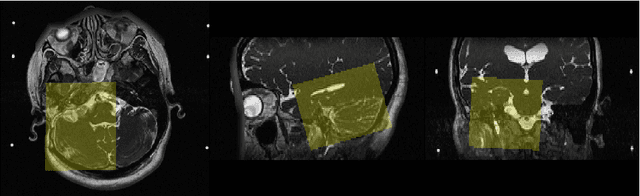

Abstract:Transcranial focused ultrasound (tFUS) is a therapeutic ultrasound method that focuses sound through the skull to a small region noninvasively and often under MRI guidance. CT imaging is used to estimate the acoustic properties that vary between individual skulls to enable effective focusing during tFUS procedures, exposing patients to potentially harmful radiation. A method to estimate acoustic parameters in the skull without the need for CT would be desirable. Here, we synthesized CT images from routinely acquired T1-weighted MRI by using a 3D patch-based conditional generative adversarial network (cGAN) and evaluated the performance of synthesized CT (sCT) images for treatment planning with tFUS. We compared the performance of sCT to real CT (rCT) images for tFUS planning using Kranion and simulations using the acoustic toolbox, k-Wave. Simulations were performed for 3 tFUS scenarios: 1) no aberration correction, 2) correction with phases calculated from Kranion, and 3) phase shifts calculated from time-reversal. From Kranion, skull density ratio, skull thickness, and number of active elements between rCT and sCT had Pearson's Correlation Coefficients of 0.94, 0.92, and 0.98, respectively. Among 20 targets, differences in simulated peak pressure between rCT and sCT were largest without phase correction (12.4$\pm$8.1%) and smallest with Kranion phases (7.3$\pm$6.0%). The distance between peak focal locations between rCT and sCT was less than 1.3 mm for all simulation cases. Real and synthetically generated skulls had comparable image similarity, skull measurements, and acoustic simulation metrics. Our work demonstrates the feasibility of replacing real CTs with the MR-synthesized CT for tFUS planning. Source code and a docker image with the trained model are available at https://github.com/han-liu/SynCT_TcMRgFUS

Abstract:Transcranial MRI-guided focused ultrasound (TcMRgFUS) is a therapeutic ultrasound method that focuses sound through the skull to a small region noninvasively under MRI guidance. It is clinically approved to thermally ablate regions of the thalamus and is being explored for other therapies, such as blood brain barrier opening and neuromodulation. To accurately target ultrasound through the skull, the transmitted waves must constructively interfere at the target region. However, heterogeneity of the sound speed, density, and ultrasound attenuation in different individuals' skulls requires patient-specific estimates of these parameters for optimal treatment planning. CT imaging is currently the gold standard for estimating acoustic properties of an individual skull during clinical procedures, but CT imaging exposes patients to radiation and increases the overall number of imaging procedures required for therapy. A method to estimate acoustic parameters in the skull without the need for CT would be desirable. Here, we synthesized CT images from routinely acquired T1-weighted MRI by using a 3D patch-based conditional generative adversarial network and evaluated the performance of synthesized CT images for treatment planning with transcranial focused ultrasound. We compared the performance of synthetic CT to real CT images using Kranion and k-Wave acoustic simulation. Our work demonstrates the feasibility of replacing real CT with the MR-synthesized CT for TcMRgFUS planning.